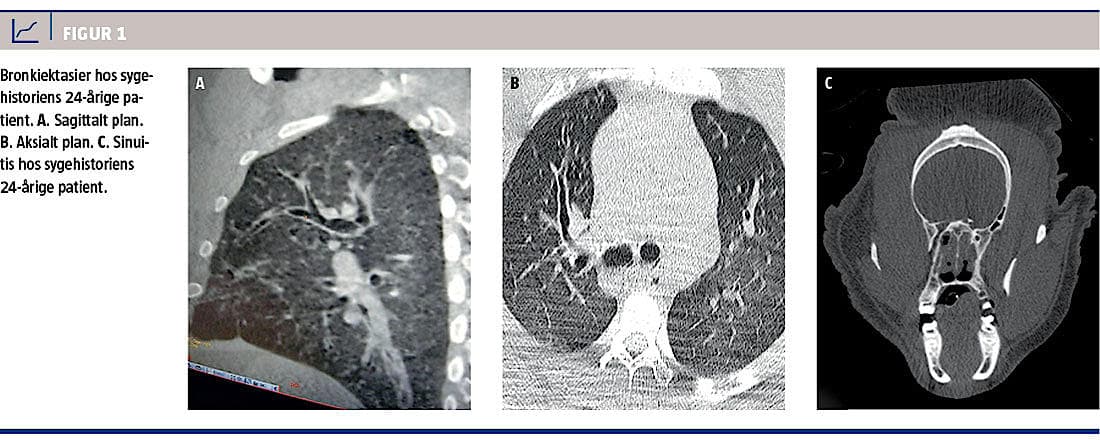

Hyppigheden af såvel øvre som nedre luftvejs-

infektioner tiltog, og patienten, der på daværende tidspunkt var 24 år, blev tiltagende alment påvirket. Det blev derfor besluttet at foretage en billeddiagnostisk undersøgelse. Han blev derfor anæsteseret, intuberet og transporteret til Aalborg Universitetshospital. Der blev foretaget CT på Nuklearmedicinsk Afdeling. Skanningen viste bilateral sinuitis af sinus maxillaris, bilateral mastoiditis og bilaterale bronkiektasier (Figur 1). Med baggrund i skanningen blev han sat i længerevarende antibiotikabehandling med azithromycin 1 g dagligt (han vejede 156 kg) og begyndte endvidere i fysiurgisk træning. Samtidig blev han anbefalet et vægttab, og kulhydratindholdet i kosten blev reduceret.